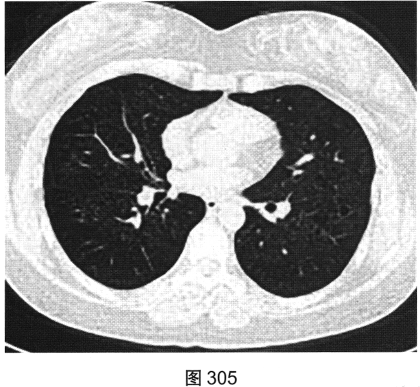

- [材料题] 患者女性,32岁,因“间断刺激性干咳1年,发现肺部囊性病变8个月”就诊。患者无发热、咯血、胸痛、呼吸困难。服甘草片、阿莫西林无明显好转。胸部HRCT如图302~图307所示。

- 多项选择题2.影像检查所示肺内主要病变的形态、分布特点为( )

A、囊状透亮影形状不规则、大小不一

C、囊状透亮影形状规则,大小及肺内分布均匀

G、囊壁较薄、略欠均匀,部分囊壁欠连续

- 多项选择题4.[提示]患者有长期吸烟史,已戒烟1年; 血ESR、CRP(一),血嗜酸性粒细胞(一), 血免疫球蛋白、免疫固定电泳及VEGF-D(一),ANA、ANCA(一); 抗dsDNA(一);腹部超声未见明显异常; 肺通气功能正常。给予拜复乐抗感染、沐舒坦化痰等对症治疗,咳嗽症状略缓解。结合患者临床及CT表现, 首先考虑诊断为( )

B、肺朗格罕细胞组织细胞增生症